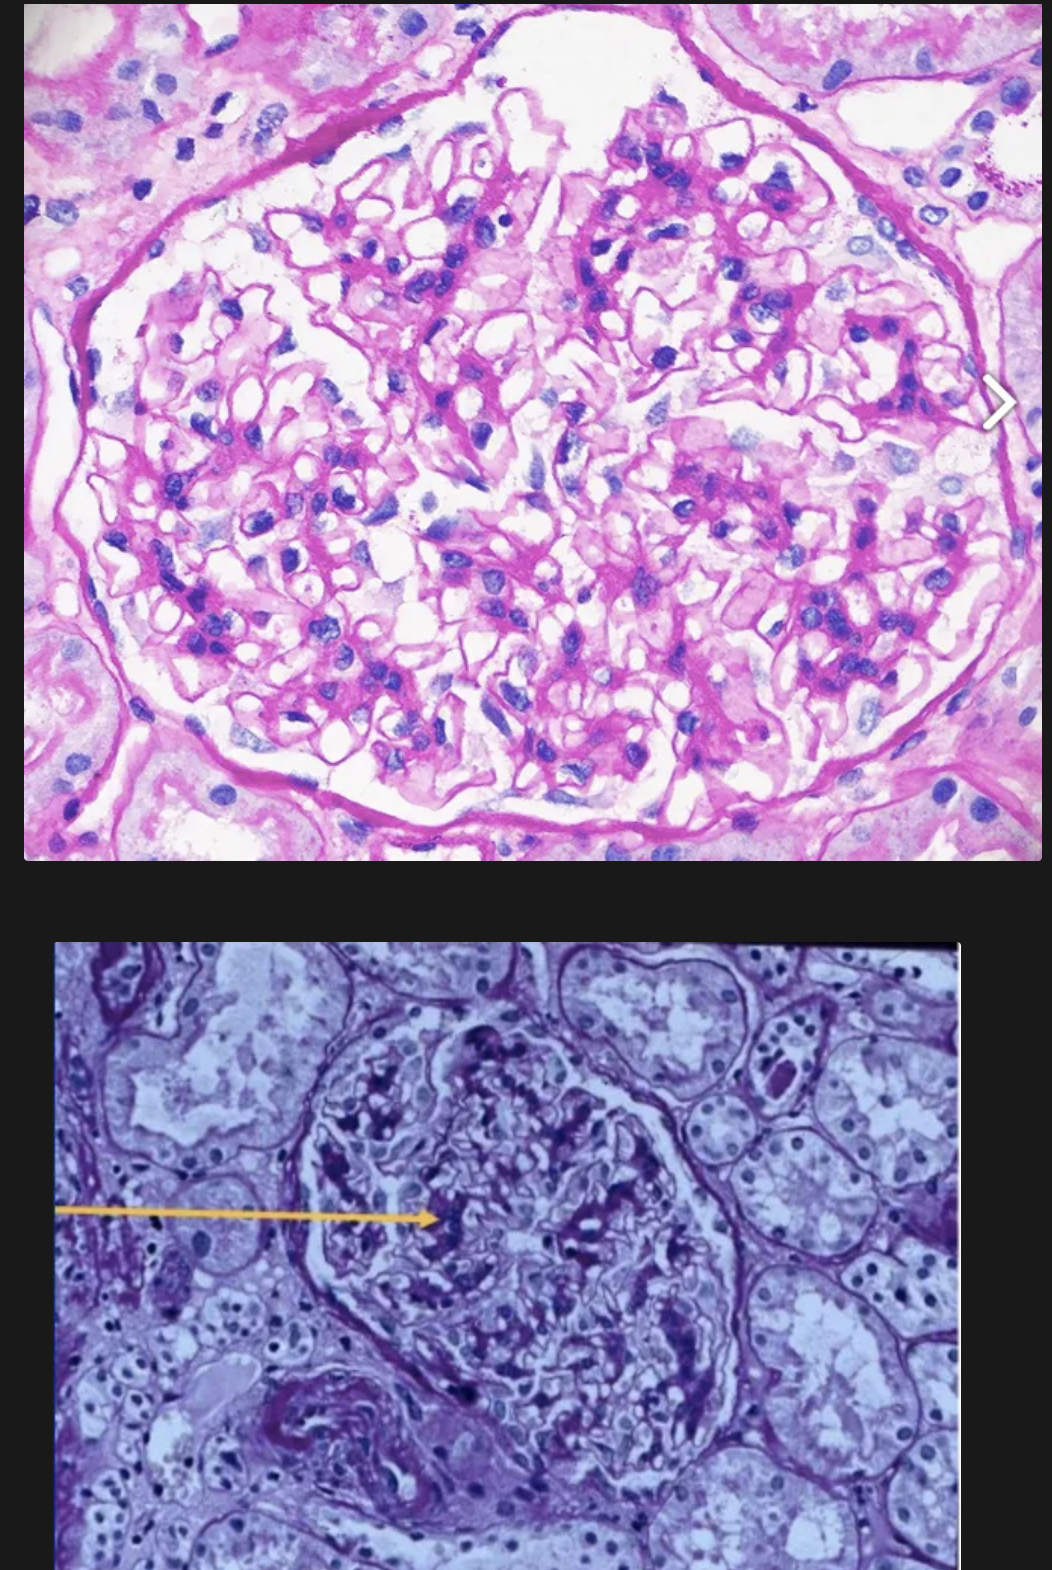

Nefritis Lúpica de clase IV

Forma más frecuente y grave

Lesiones similares a las de clase 3, pero la afectación es difusa osea >50% de los glomérulos afectados

Lesiones pueden ser segmentarias (IV-S) o globales (IV-G)

Proliferación de células endoteliales, mesangiales y epitelilales

se pueden formar semilunas es espacio de Bowman

Engrosamiento de la pared capilar a forma de “asa de alambre“ en microscopía óptica

Hay inmunocomplejos por inmunofluorescencia